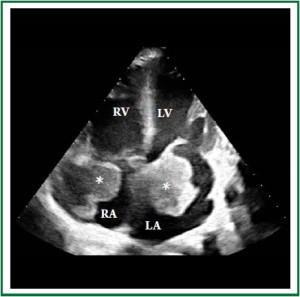

A 46-year-old Caucasian male was admitted to the emergency room with progressive dyspnea, lower limb edema and intermittent fever for 1 month. Past medical history included HIV infection for 20 years, with irregular highly active antiretroviral therapy (HAART) treatment. He had a history of smoking, alcoholism and cocaine addiction. On physical examination, the patient presented with a rapid respiratory rate, blood pressure of 118×68 mmHg and heart rate of 104 bpm. Laboratory data revealed hemoglobin concentration of 6.7 g/dl, white blood cell count of 3.600 /mm3 and platelet count of 22.000 /mm3, with a CD4 count of 49 cels /μl. Computed tomography demonstrated a large, infiltrative, solid mass involving the ascending aorta, pulmonary artery, right ventricle and both atria (Figure 1 and Figure 2) with a lymph node conglomerate in the anterior mediastinum. Transthoracic echocardiography revealed biatrial dilation, mild left ventricular hypokinesia and severe right ventricular impairment. A large echodense mass with irregular borders filled almost completely the left atrium (Figure 3), while another mass was observed inside the right atrium (Figure 4), both attached to the interatrial septum. Increased transvalvular mitral and tricuspid gradients were observed by Doppler study. HAART was started along with intratechal methotrexate, followed by intravenous dexamethasone. Mediastinal biopsy revealed a HHV8-positive PBL. Tumoral cells showed positivity for immunohistochemical markers HHV8, MUM-1, CD138 (focal), CD20 (focal) and Ki67 (high index), whereas CD3 and Epstein-Barr virus (EBV) resulted negative. Bone marrow biopsy showed rare neoplastic cells, compatible with interstitial infiltration by HHV8-positive PBL. Chemotherapy with cyclophosphamide was started. A control echocardiogram after 3 days showed no tumor regression, but significant deterioration of systolic ventricular function. The patient developed hemodynamic instability and worsening of respiratory pattern, requiring ventilatory and hemodynamic support. Despite therapy, the patient died the following day.

Figure 4. Two-dimensional echocardiographic apical 4-chamber view showing the tumor (*) invading both atria.